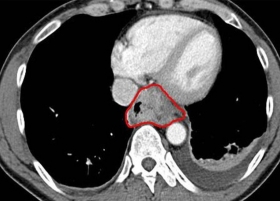

Read MoreThis Computer Program Detects Cancer Earlier Than Ever—Without Surgery

Cancer is often found when someone starts to feel symptoms—pain, an abnormal growth, or maybe just fatigue. Now scientists have developed a computer program that could i...